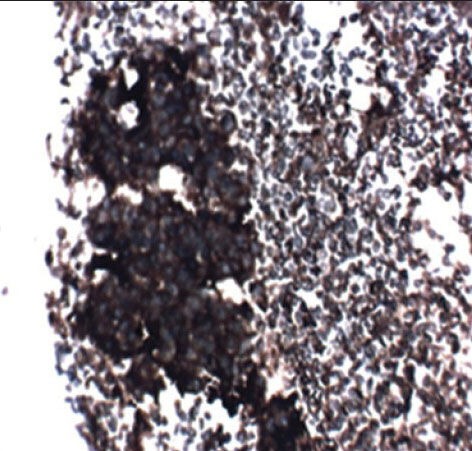

The case we present here is a 13-year-old boy who presented with the complaints of left lower limb weakness for 5 months and low back pain for 6 months. Hemogram and biochemical parameters were normal except lactate dehydrogenase (LDH) showing value of 96.40/IU/L, magnetic resonance imaging of the spine showed a large mass in presacral lesion (8 cm × 7 cm × 9 cm), with destruction of the sacrum (S2 S3 and S4) with interspinal extension. Bone scan showed multiple pelvic bone lesions, radiograph of chest, ultrasound of abdomen, pelvis and electrocardiogram were within normal limits. Bone marrow was not involved. Fine-needle aspiration cytology of the mass proved it to be a small round cell tumor. Immunohistochemistry for MIC2 was positive. Synaptophysin was inconclusive and leukocyte common antigen, desmin were negative [Figure [Figure1a1a and andbb].

| Figure 1a:EWSR1 partners and tumorsCell block of Ewing's sarcoma (H and E)